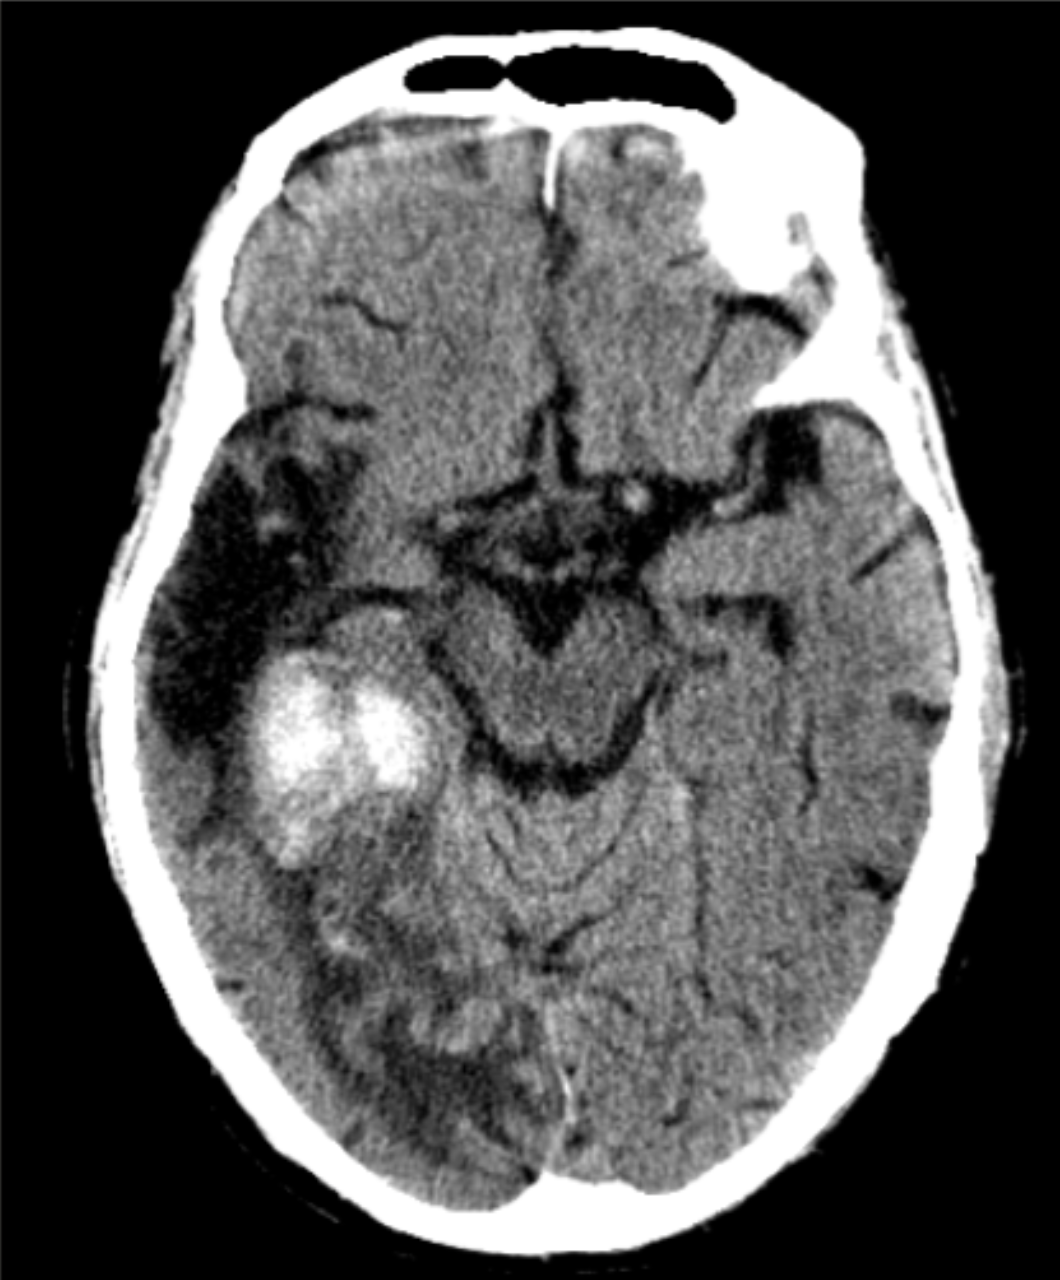

68 y/o F with left sided visual hallucinations.

Hemorrhagic conversion of PCA ischemic stroke